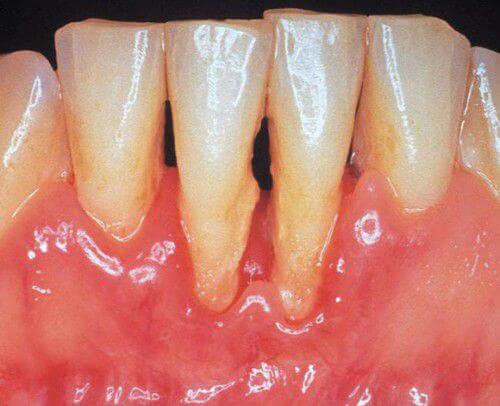

Biểu hiện cơ bản của tình trạng viêm loét chân răng là khi đánh răng, phần nướu đỏ, sưng, nướu có xu hướng tách ra khỏi răng, có ổ mủ hoặc có mủ chảy ra ở giữa răng và nướu ở vùng cổ răng. Răng khi bị viêm sẽ trở nên nhạy cảm với các loại đồ ăn nóng, lạnh, chua, ngọt.

Khi viêm chân răng ở mức nghiêm trọng thì răng có xu hướng lung lay hoặc thưa ra, có nhiều trường hợp nướu bị tụt khiến cho chân răng có cảm giác như dài ra. Nếu muốn biết thêm chi tiết hơn về biểu hiện viêm loét chân răng hãy gửi câu hỏi đến cho các bác sĩ nha khoa giải đáp thêm.